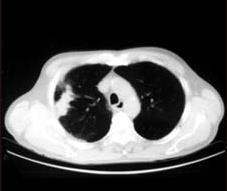

TheproposedsystemismethodicallytestedusingdifferentlungnoduleCTimage.

Fig.1CTscansLungNoduleImages